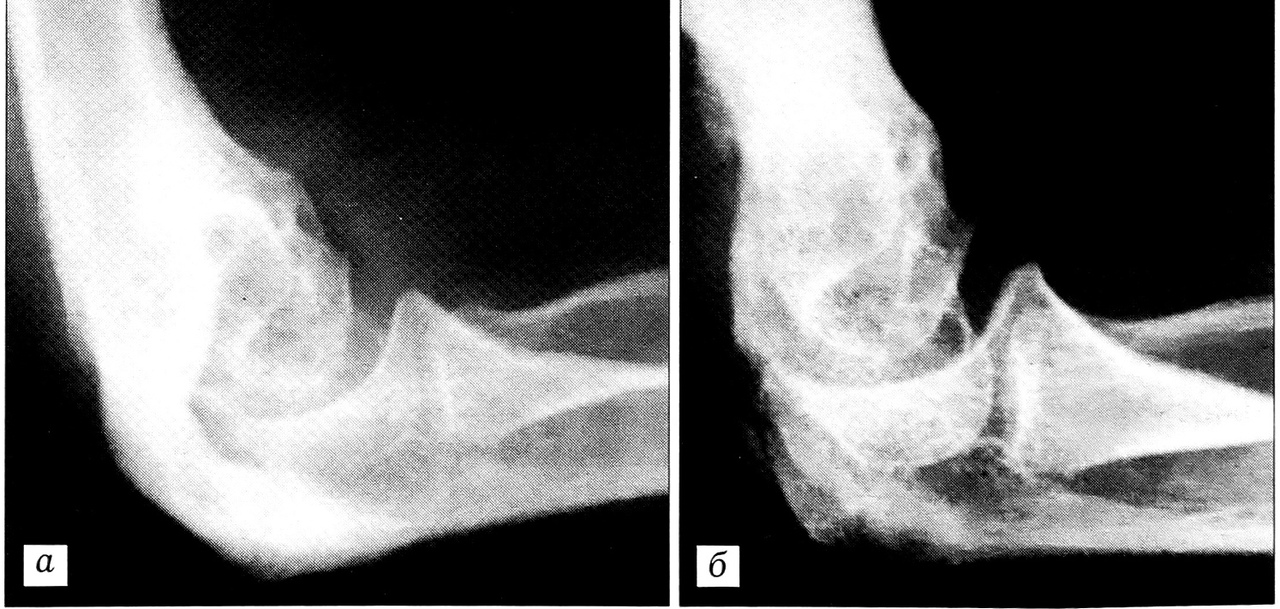

При внесуставном анкилозе у 8 (12,3%) больных произведено удаление оссификата с артролизом и формированием ямок плечевой кости (рис. 1). У 4 (6,1%) больных ямки плечевой кости оказались полностью заполненными костной тканью. У этих пациентов произведено удаление оссификата с формированием «сквозного» канала в дистальном отделе плечевой кости (рис. 2).

Рис. 2. Рентгенограммы локтевого сустава больного М.: а — до операции; б — после операции: удаления оссификата в сочетании с формированием «сквозного» канала в дистальном отделе плечевой кости.